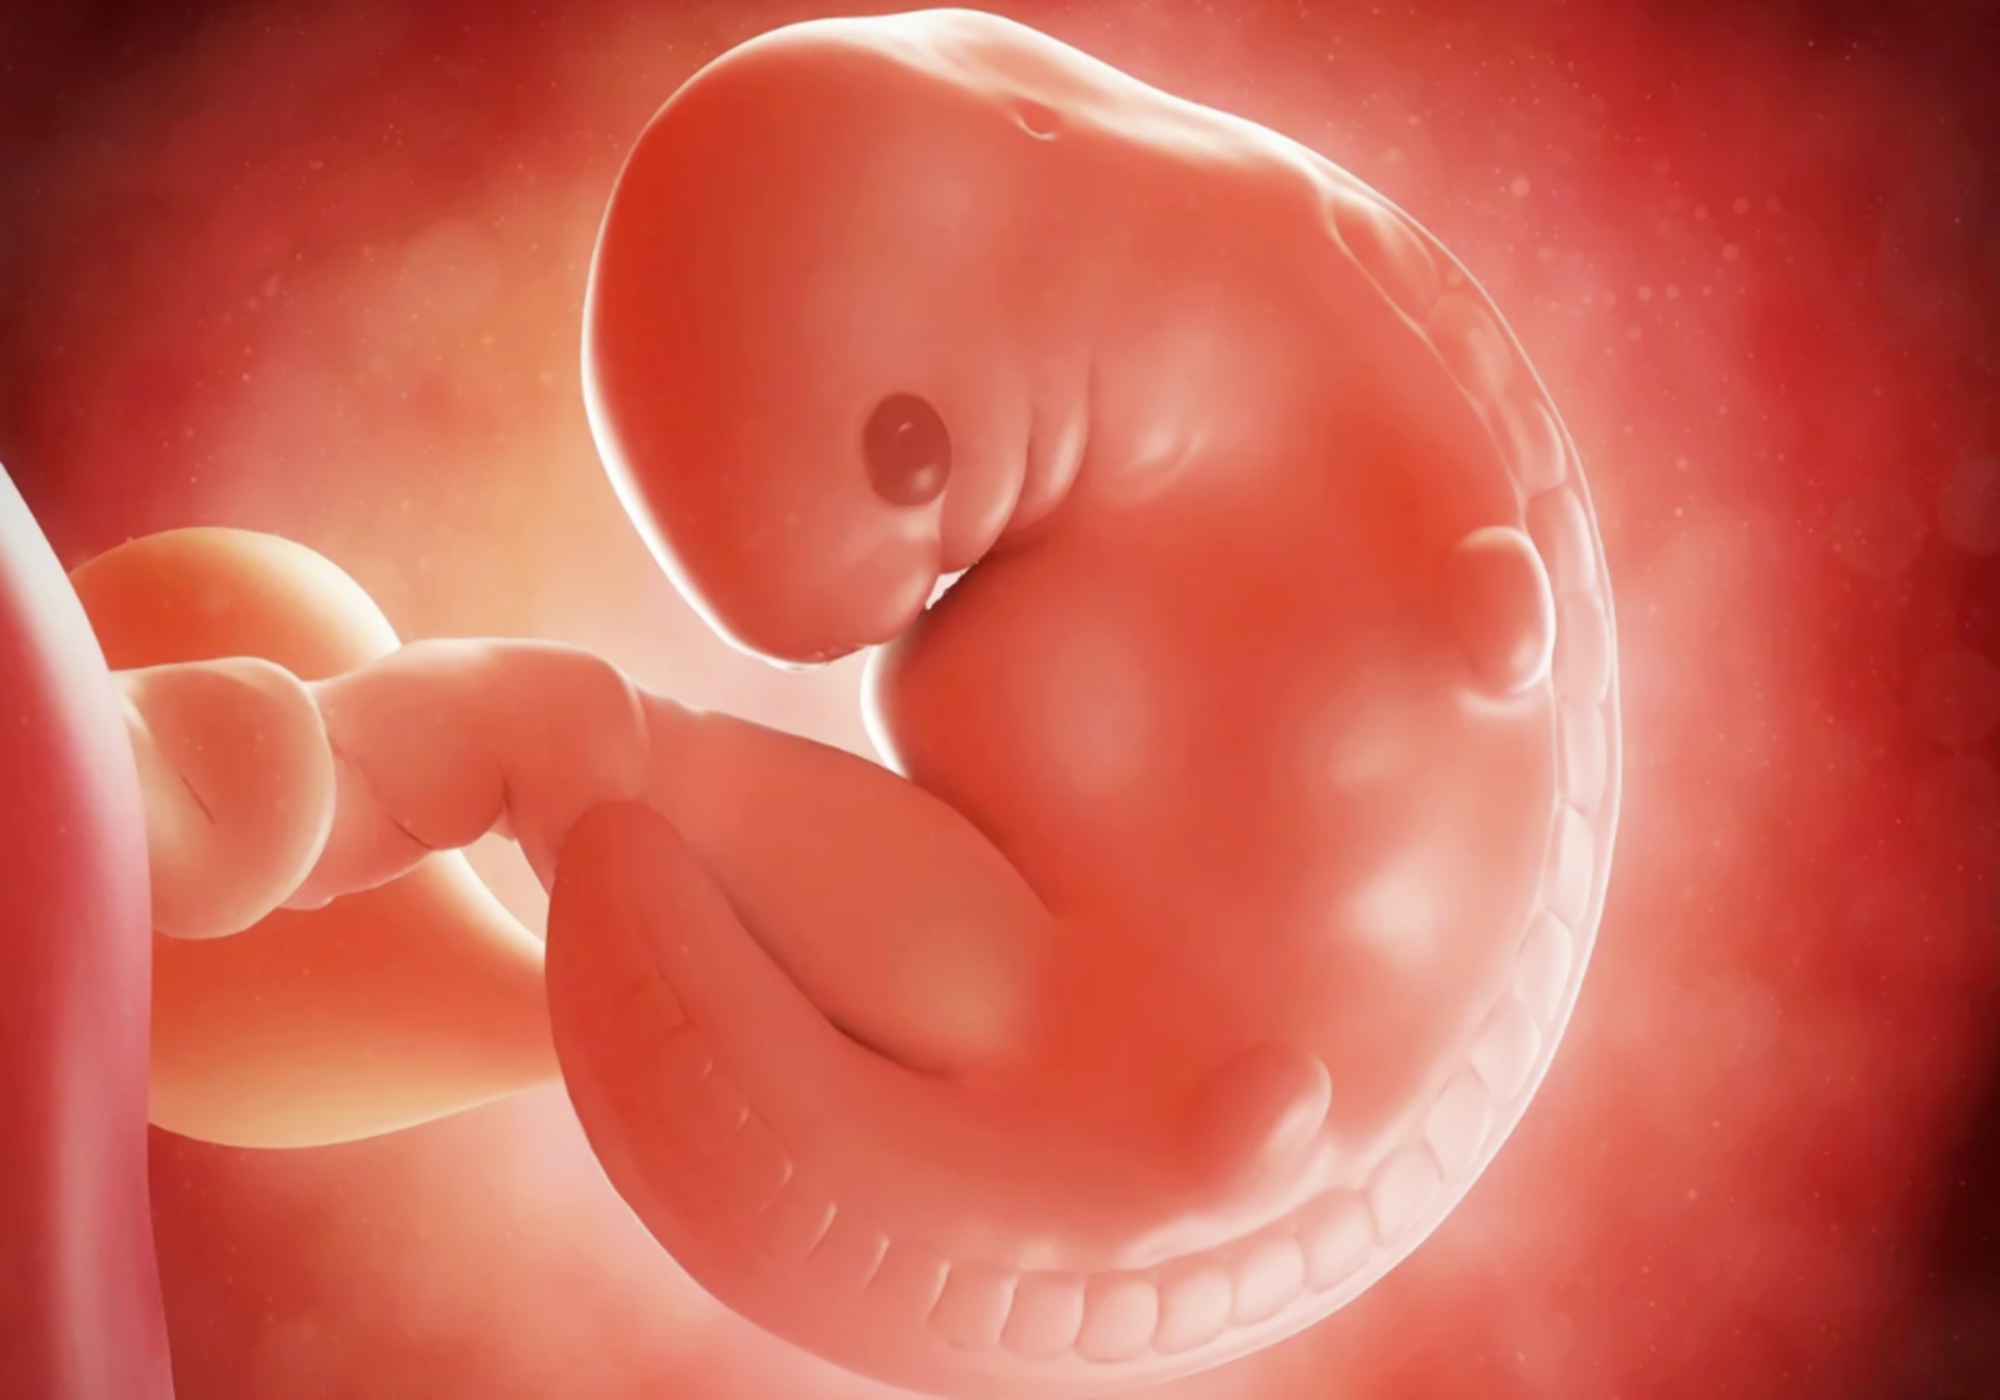

▶什么是胎芽、胎心?胎芽胎心是胚胎发育过程中的一个状态

在最初的2周是我们把胚胎称之为孕卵,而随着胚胎中器官的不断成长发育,与囊、胎芽、胎心也就会逐步出现。

- 怀孕30-40天---孕囊形成

- 怀孕40-50天---胎芽形成

- 怀孕50-60天---胎心出现

一般情况下,在孕6-7周的时候,就可以看得到胎芽以及胎心搏动,如果未检测到胎芽或者胎心,就有可能是个空胎囊,一些原因阻挡了他们成长,他就像一颗坏掉的种子一样,没有办法在妈妈的肚子里生根发芽,而这种情况就可能会终止妊娠。